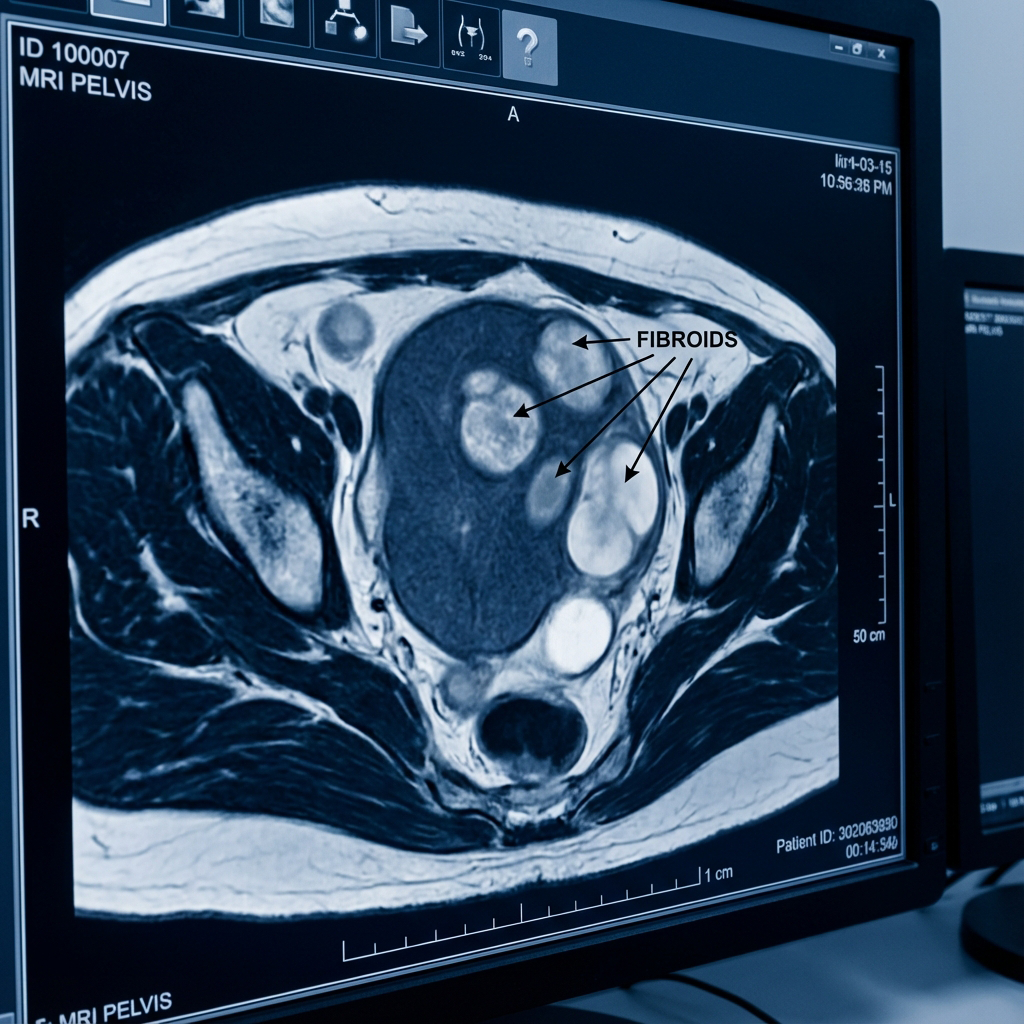

بعد إجراء الفحص السريري وعمل أشعة الرنين المغناطيسي (MRI)، تبين وجود ثلاثة أورام ليفية كبيرة الحجم تضغط على جدار الرحم وتعد المصدر الرئيسي للنزيف والألم.

صورة الأشعة قبل التدخل